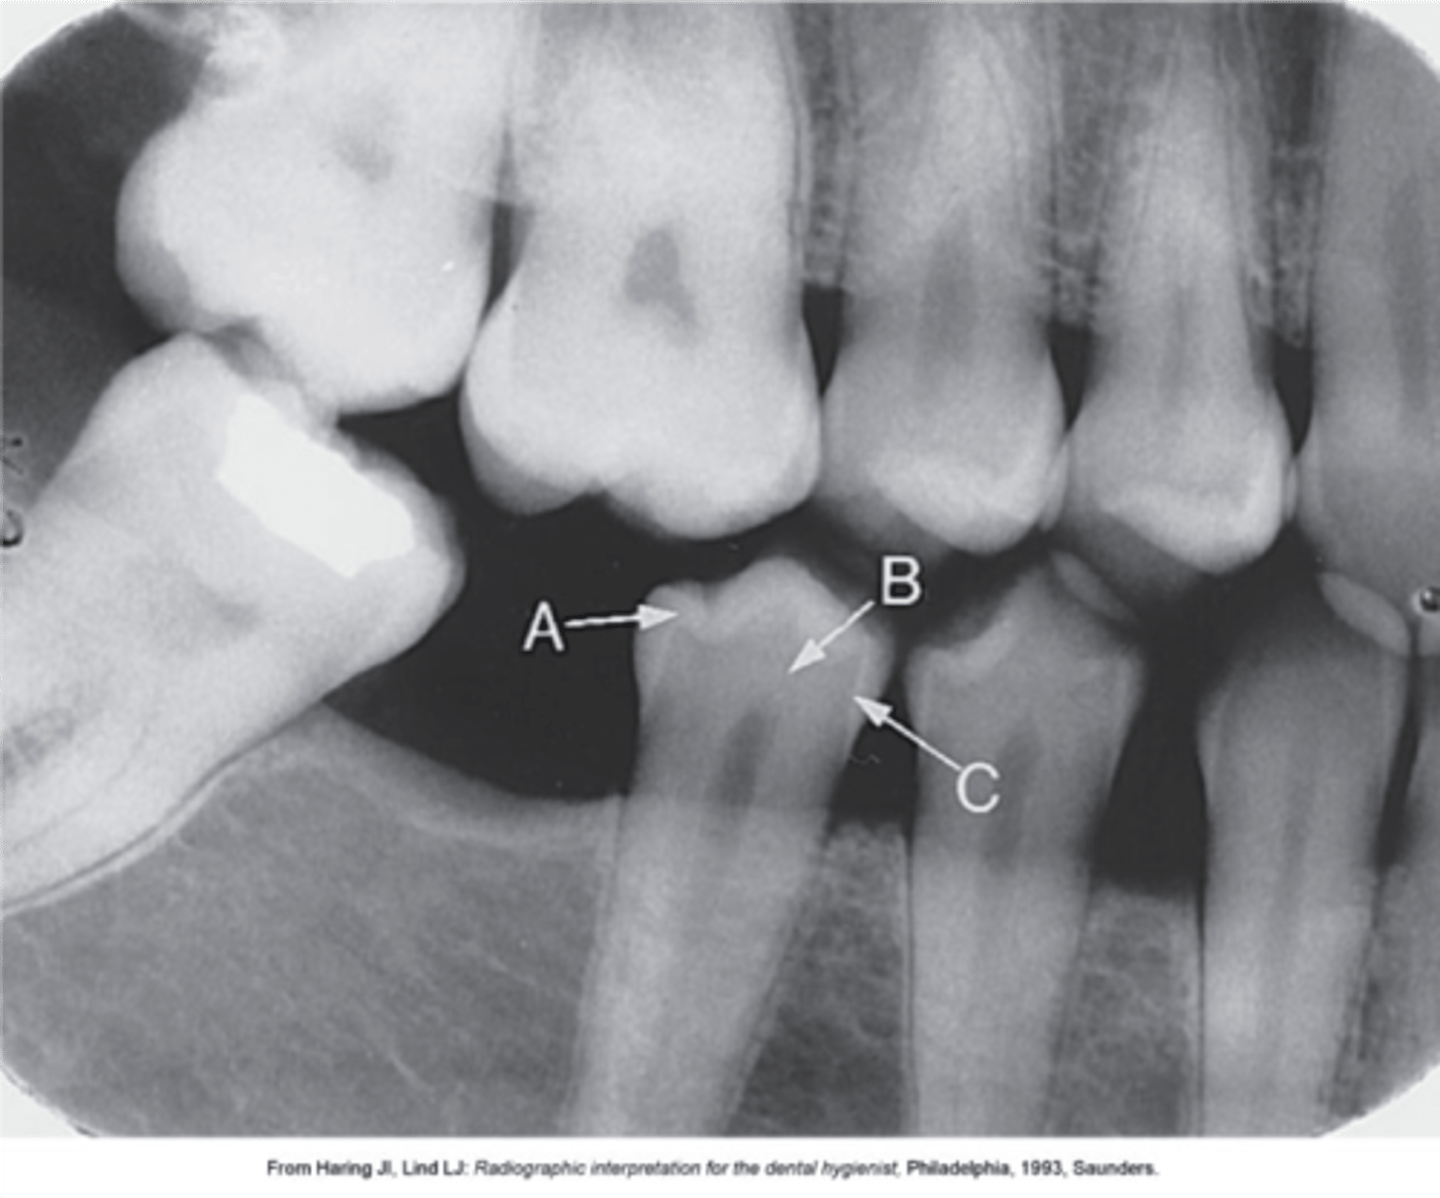

Enamel

What is arrow A pointing to?

Dentin

What arrow B pointing to?

Pulp cavity

What is the radiolucent structure shown here?

Dentino-enamel junction (DEJ)

What arrow C pointing to?